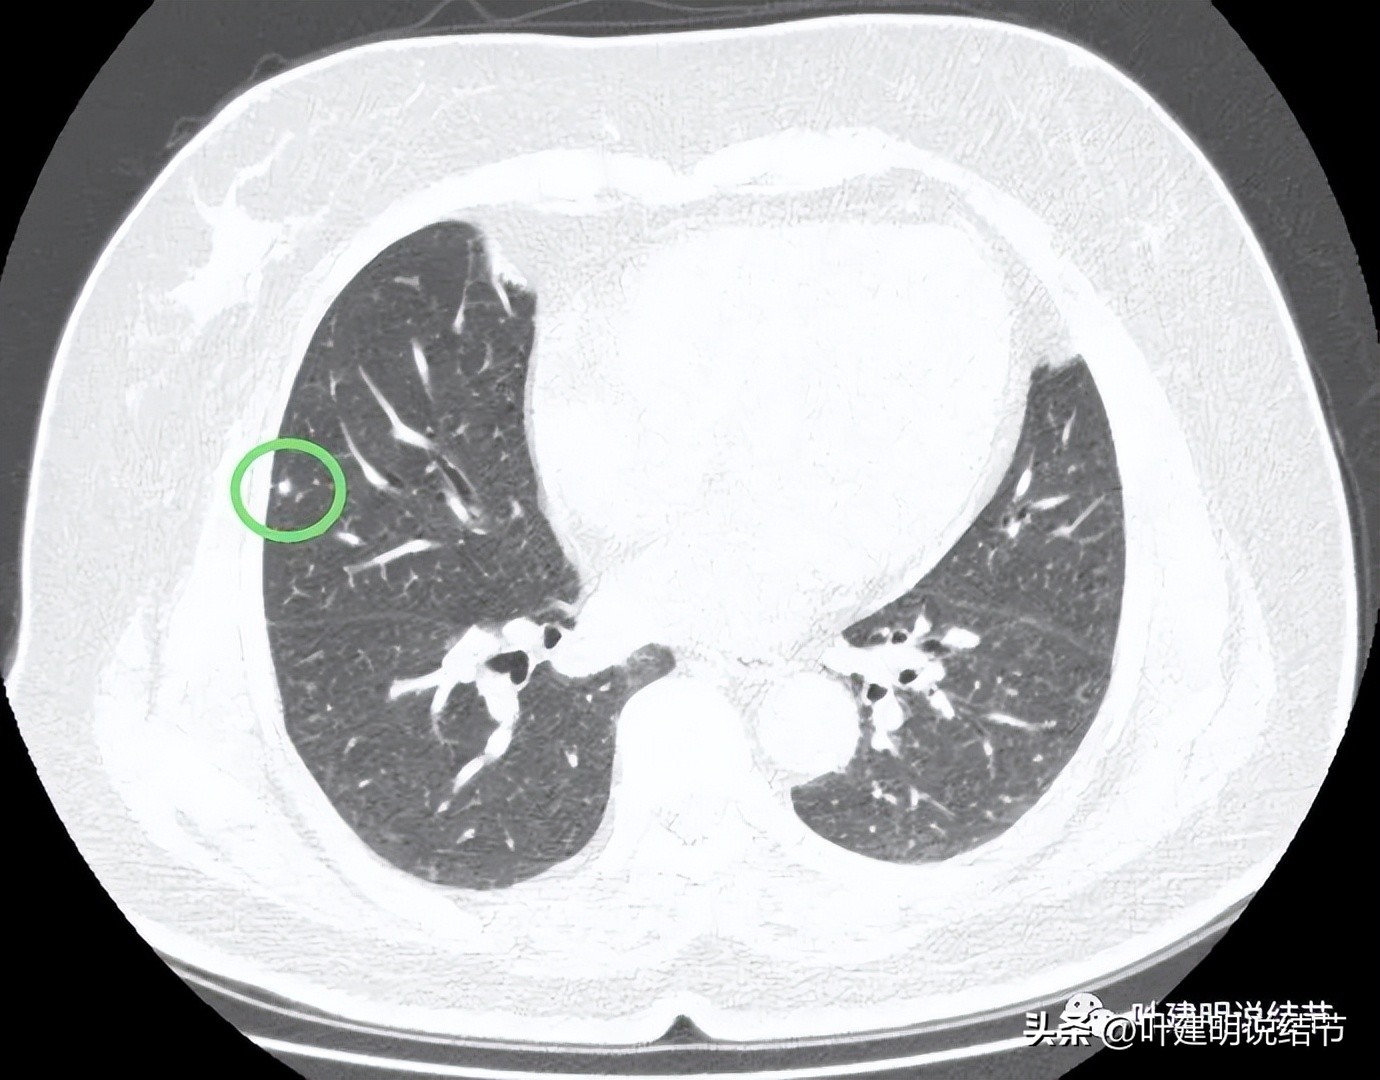

病灶1:右上叶实性小结节,密度高,胸膜下,考虑良性可能性大

病灶2:右中叶微小实性结节,考虑纤维增生结节可能性大